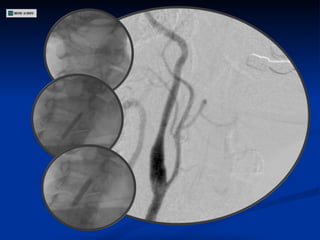

ECODOPPLER DE VASOS DEL CUELLO Estenosis 80-90 % en segmento inicial de Carótida Interna Derecha Estenosis 50-60 % en Carótida Interna Izquierda Carótidas externas permeables con flujos conservados Arterias Vertebrales permeables

Angiografía

CONDUCTA

ECODOPPLER DE VASOSDEL CUELLO Estenosis 80-90 % en segmento inicial de Carótida Interna Derecha Estenosis 50-60 % en Carótida Interna Izquierda Carótidas externas permeables con flujos conservados Arterias Vertebrales permeables